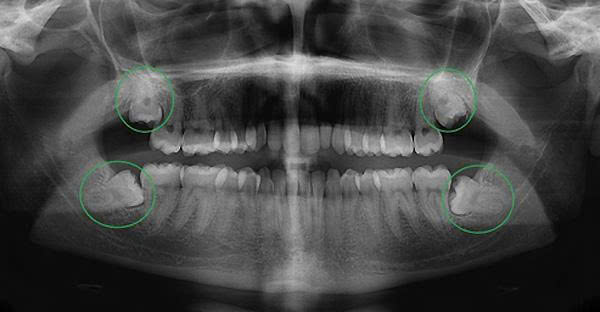

Các hướng mọc thường gặp của răng khôn mọc lệch gồm:

- Mọc nghiêng về phía răng số 7

- Mọc ngang trong xương

- Mọc ngầm dưới nướu

- Chỉ trồi lên một phần gây viêm

Các dạng răng khôn mọc lệch phổ biến

Mọc lệch gần

Răng nghiêng về phía răng số 7 → dễ gây sâu răng kế bên

Mọc ngang

Răng nằm ngang trong xương → gây đau nhiều, bắt buộc nhổ răng khôn

Mọc lệch xa

Răng nghiêng ra sau → khó vệ sinh

Mọc ngầm

Răng không trồi lên → dễ gây u nang